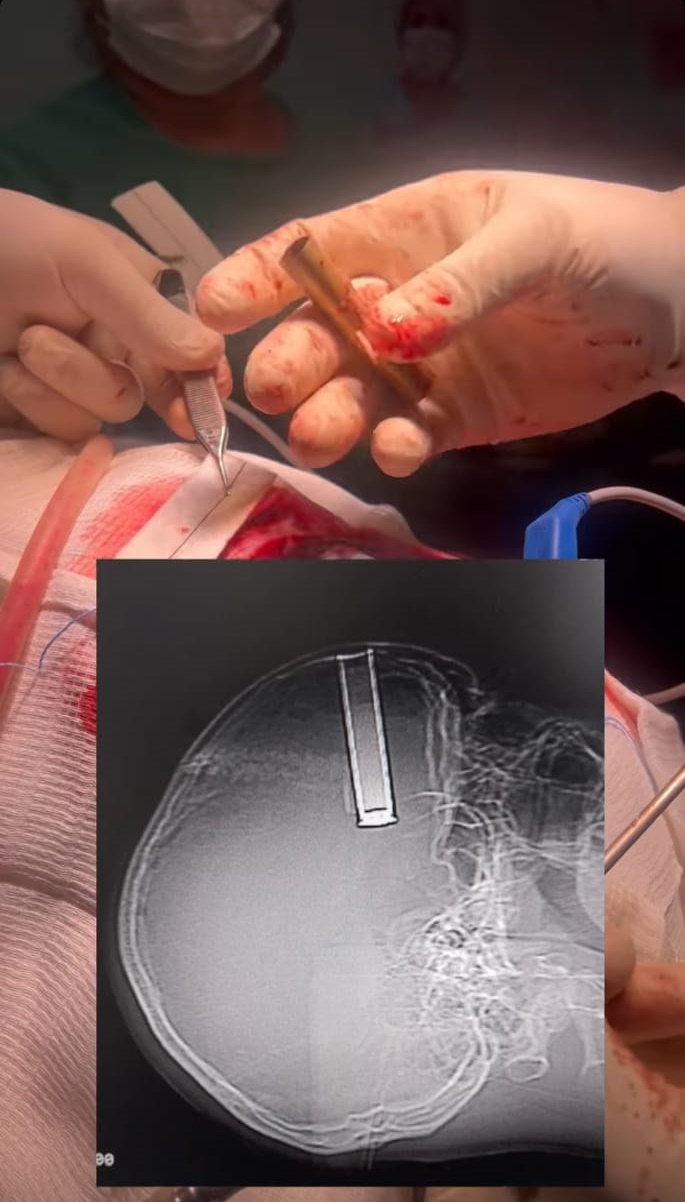

Segundo informações, durante o disparo de espingarda, o cartucho voltou e adentrou na região frontal do seu crânio. Vale destacar que o cartucho possuía aproximadamente 10 cm.

Dessa forma, o jovem passou por um procedimento cirúrgico, sendo atendido pelo Neurocirurgião Dr. Caio Nuto que realizou a cirurgia inédita com total sucesso. Além disso, o médico relatou que durante suas pesquisas e estudos, não localizou cirurgias semelhantes à essas.

“A cirurgia foi muito complexa. Possuía grande risco de morte visto que o cartucho poderia estar comprimindo uma artéria cerebral causando sangramentos, além do risco de sequelas”, informou o médico.

Durante o primeiro dia de pós-operatório, o paciente encontra-se estável, conversando e movimentando todos os membros, aparentemente não possui sequelas da cirurgia.